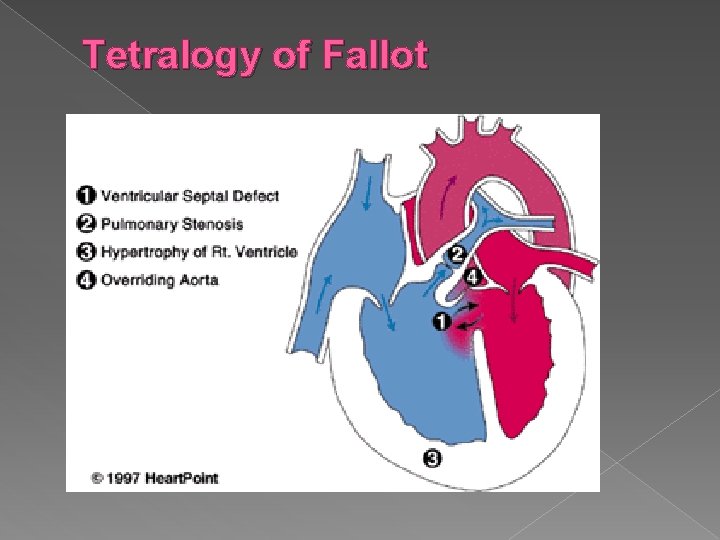

Other Cardiac Anomalies Some other conditions that can be diagnosed using ultrasound: Endocardial Cushion Defects › Atrial and ventricular septal defects resulting from failure of the common AV orifice to separate into mitral and tricuspid valves. Associated with an increased risk of Trisomy 21. Tetralogy of Fallot › Consists of four anatomic abnormalities: Large VSD, overriding aorta, pulmonary infundibular stenosis, right ventricular hypertrophy. Ebstein’s Anomaly � Downward displacement of the septal and posterior leaflets of the tricuspid valve

Tetralogy of Fallot The tetralogy of Fallot (TOF) is a congenital heart defect which classically has four anatomical components. It is the most common cyanotic heart defect and the most common cause of blue baby syndrome. � It was described in 1672 by Niels Stensen and in 1888 by the French physician Etienne Fallot, for whom it is named. � As classically described, tetralogy of Fallot involves four heart malformations which present together: �

1. A ventricular septal defect (VSD): a hole between the two bottom chambers (ventricles) of the heart. The defect is centered around the 'outlet septum', the most superior aspect of the septum, and in the majority of cases is single and large. In some cases septal hypertrophy can narrow the margins of the defect

2. Pulmonic stenosis: Right ventricular outflow tract obstruction, a narrowing at (valvular stenosis) or just below (infundibular stenosis) the pulmonary valve. The stenosis is the major cause of the malformations, with the other associated malformations acting as compensatory mechanisms to the pulmonic stenosis. The degree of stenosis varies between individuals with TOF, and is the primary determinant of symptoms and severity. This malformation is infrequently described as subpulmonary stenosis or subpulmonary obstruction.

3. Overriding aorta: An aortic valve with biventricular connection, that is, it is connected to the right ventricle as well as the left ventricle. The degree to which the aorta is attached to the right ventricle is called "override. " The aortic root can be displaced anteriorly or it can override the septal defect, but it is still to the right of the root of the pulmonary artery. The degree of override is quite variable, with 5 -95% of the valve being connected to the right ventricle.

4. Right ventricular hypertrophy: The right ventricle is more muscular than normal, causing a characteristic boot-shaped appearance as seen by chest X-ray. Due to the misarrangement of the external ventricular septum, the right ventricular wall increases in size to deal with the increased obstruction to the right outflow tract. This feature is now generally agreed to be a secondary anomaly, as the level of hypertrophy generally increases with age.

Tetralogy of Fallot 4 anatomic abnormalities � Large VSD � Overriding aorta � Pulmonary stenosis � Right ventricular hypertrophy